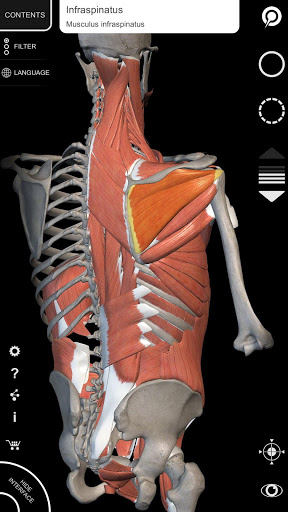

"Anatomía - Atlas 3D" permite estudiar la anatomía humana de forma fácil e interactiva.

A través de una interfaz sencilla e intuitiva es posible observar cada estructura anatómica desde cualquier ángulo.

Los modelos anatómicos 3D son especialmente detallados y con texturas de hasta una resolución de 4k.

La subdivisión por regiones y las vistas predefinidas facilitan la observación y el estudio de partes individuales o grupos de sistemas y las relaciones entre los diferentes órganos.

• Sistema musculoesquelético